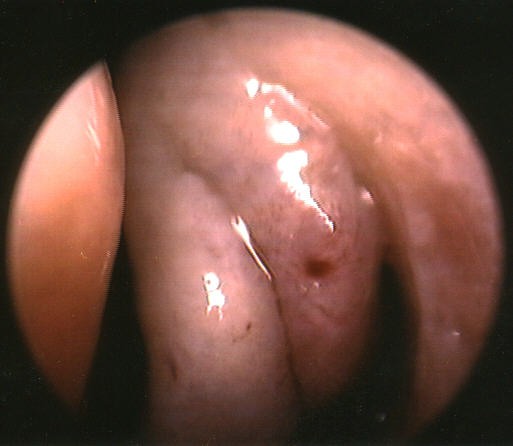

The picture above demonstrates the natural drainage pathway for the bulla ethmoidalis: the majority of the anterior ethmoid cell system. It typically drains posteriorly into the retro-bullar space. The probe is seen passing into the retro-bullar space and the tip is seen through the drainage pathway. This is on the patient's left side. These are very normal findings, but they are not often visualized this well, or discussed in textbooks. |